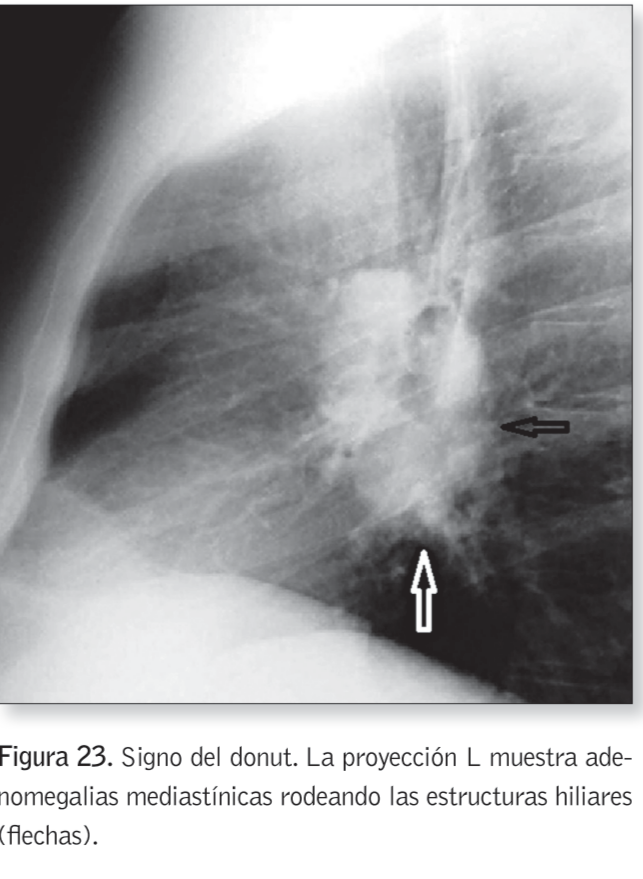

Signo del Donut

¿Cuándo se da el signo del donut?

Cuando hay adenomegalias mediastinicas